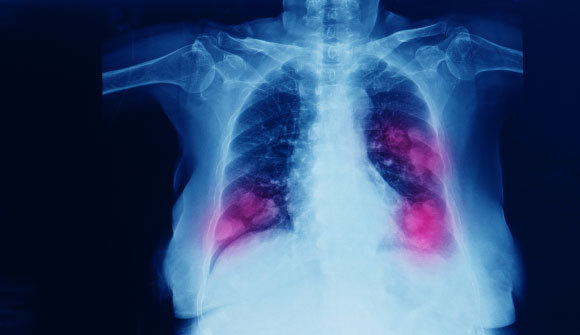

هكذا يبدو السرطان الأكثر فتكًا في العالم، ومسبّب الموت الرائد في البلاد. سرطان رئة ثنائيّ كما يظهر في تصوير الرونتجن| Yok_onepiece, Shutterstock